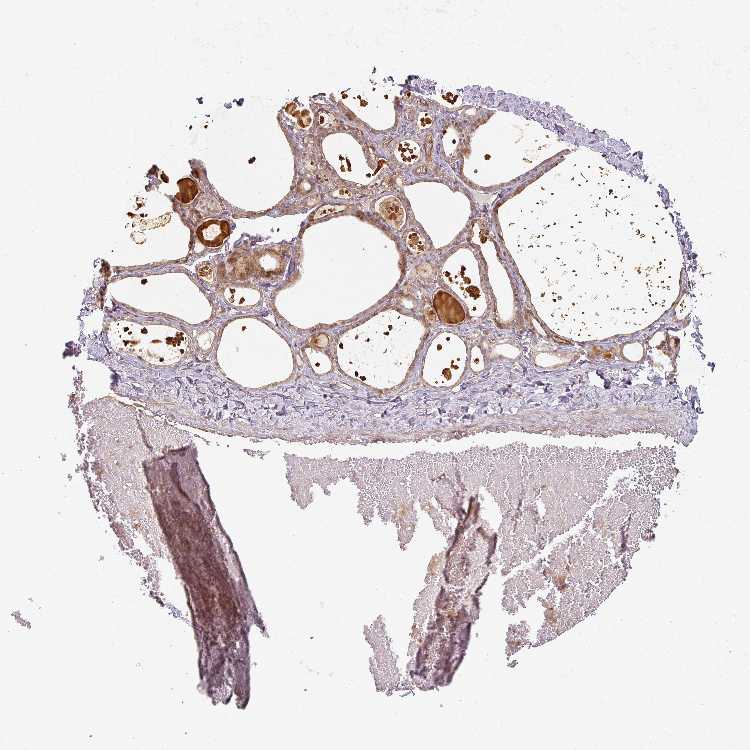

CNOT1